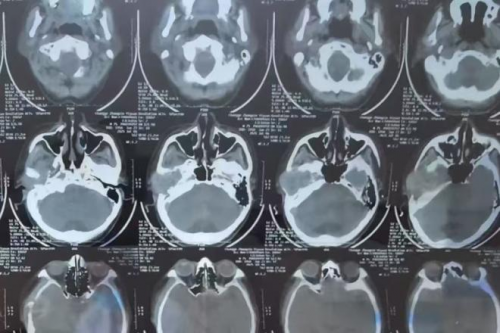

郑州民生耳鼻喉医院特聘专家娄卫华教授负责接诊,并根据张大爷的描述安排了详细检查。通过CT影像和耳内窥镜分析,发现张大爷的右侧颞骨处存在一个肿物。结合影像学结果及病史,娄教授诊断为“右侧颞骨肿瘤”,建议立即手术切除,同时做病理检测以明确肿物性质。

颞骨属于解剖构造复杂的区域,紧邻多条关键神经与血管,因此手术风险极高。为了确保手术安全开展,娄卫华教授组织团队针对张大爷的病情进行了深入讨论,最终制定了一套合理的手术方案,既保证肿物能够完整切除,又尽量减少对周围组织的损伤。